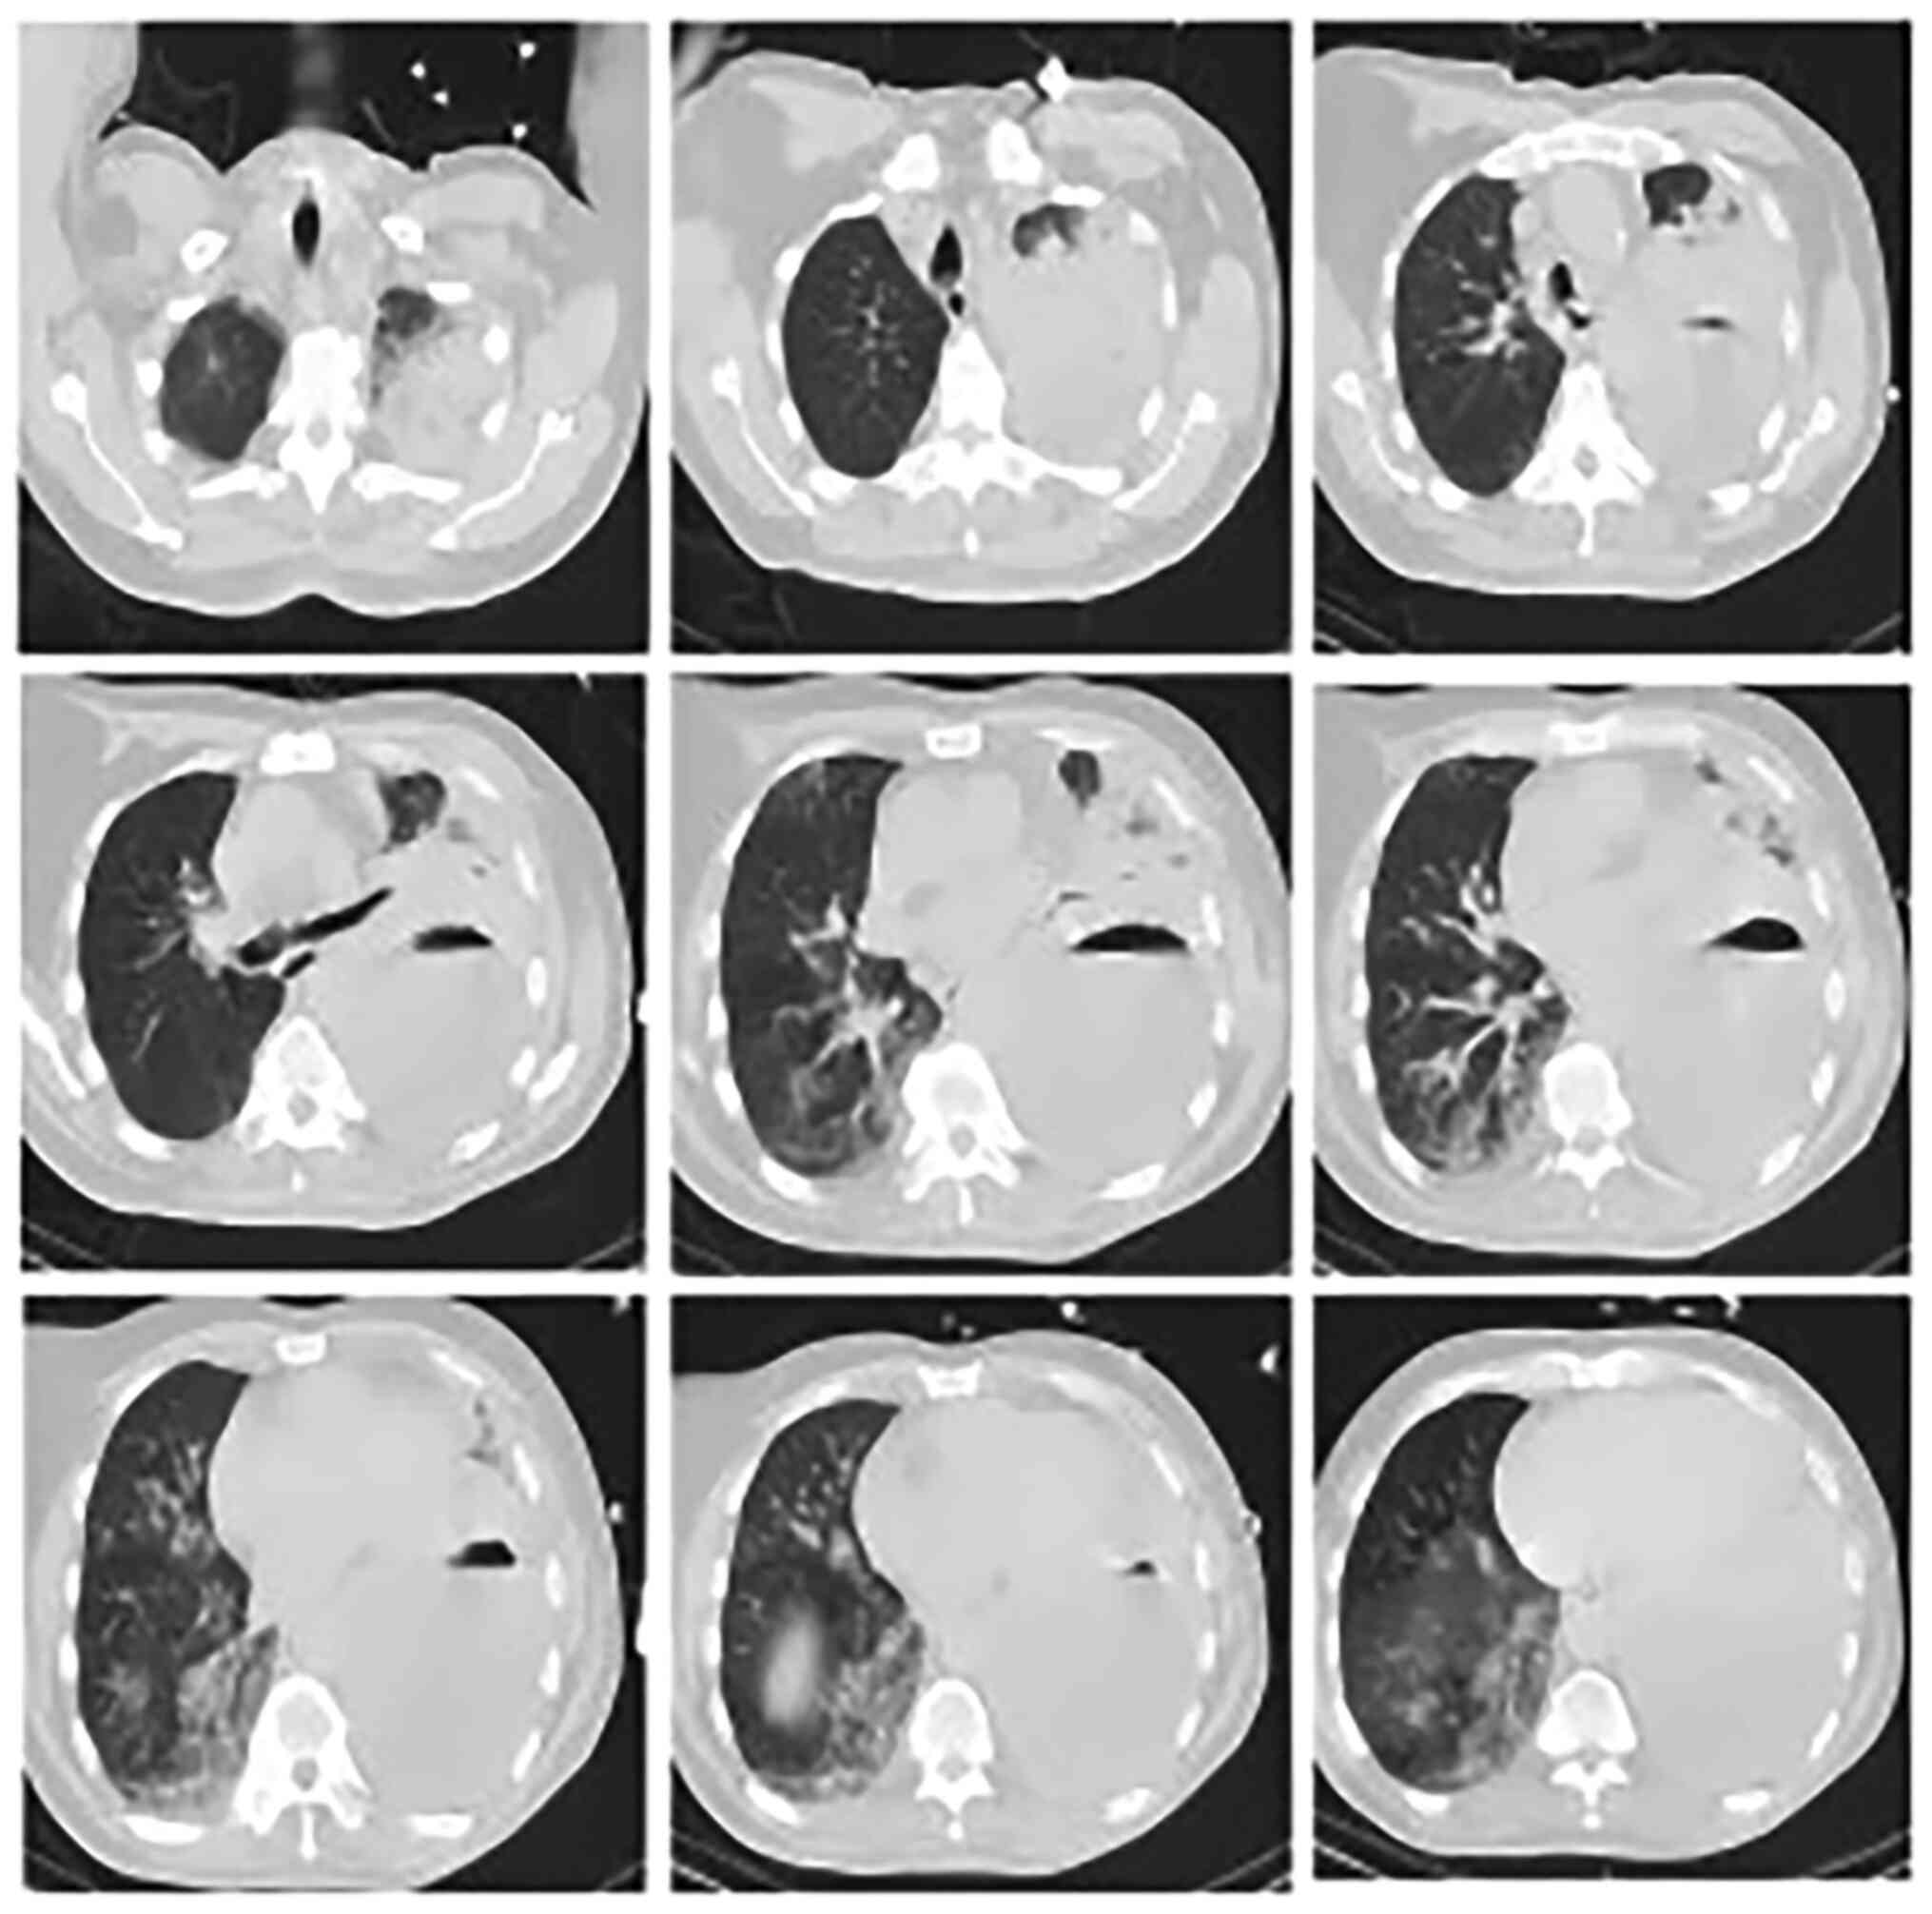

A 51-year-old man was admitted to emergency intensive care unit (EICU) of the Second Affiliated Hospital of Jiaxing University (Jiaxing, China) in July, 2020, due to a cough accompanied by left chest pain and high fever. On the afternoon of admission, he experienced sudden shortness of breath and a cough with yellow purulent foul-smelling sputum accompanied by systemic profuse sweating. Chest computed tomography (CT) was performed immediately (Fig. 1) and showed a left upper lung abscess and left empyema, considered indicative of infection. A cardiac color ultrasound showed blunt and paradoxical apex movement and mild aortic valve, mitral valve, and tricuspid regurgitation. His blood tests showed metabolic acidosis and hypoxemia and white blood cell (WBC) count of 65.5x109/l. The patient had a history of ankylosing spondylitis, a kind of autoimmune disease, and had been taking immunosuppressive drugs, including salazosulfadimidine and adrenocortical hormone. However, his family medical history was unremarkable.

Figure 1

Chest computed tomography images of the patient on admission showing a large left pleural effusion, left lung consolidation, and right lower lung infection.